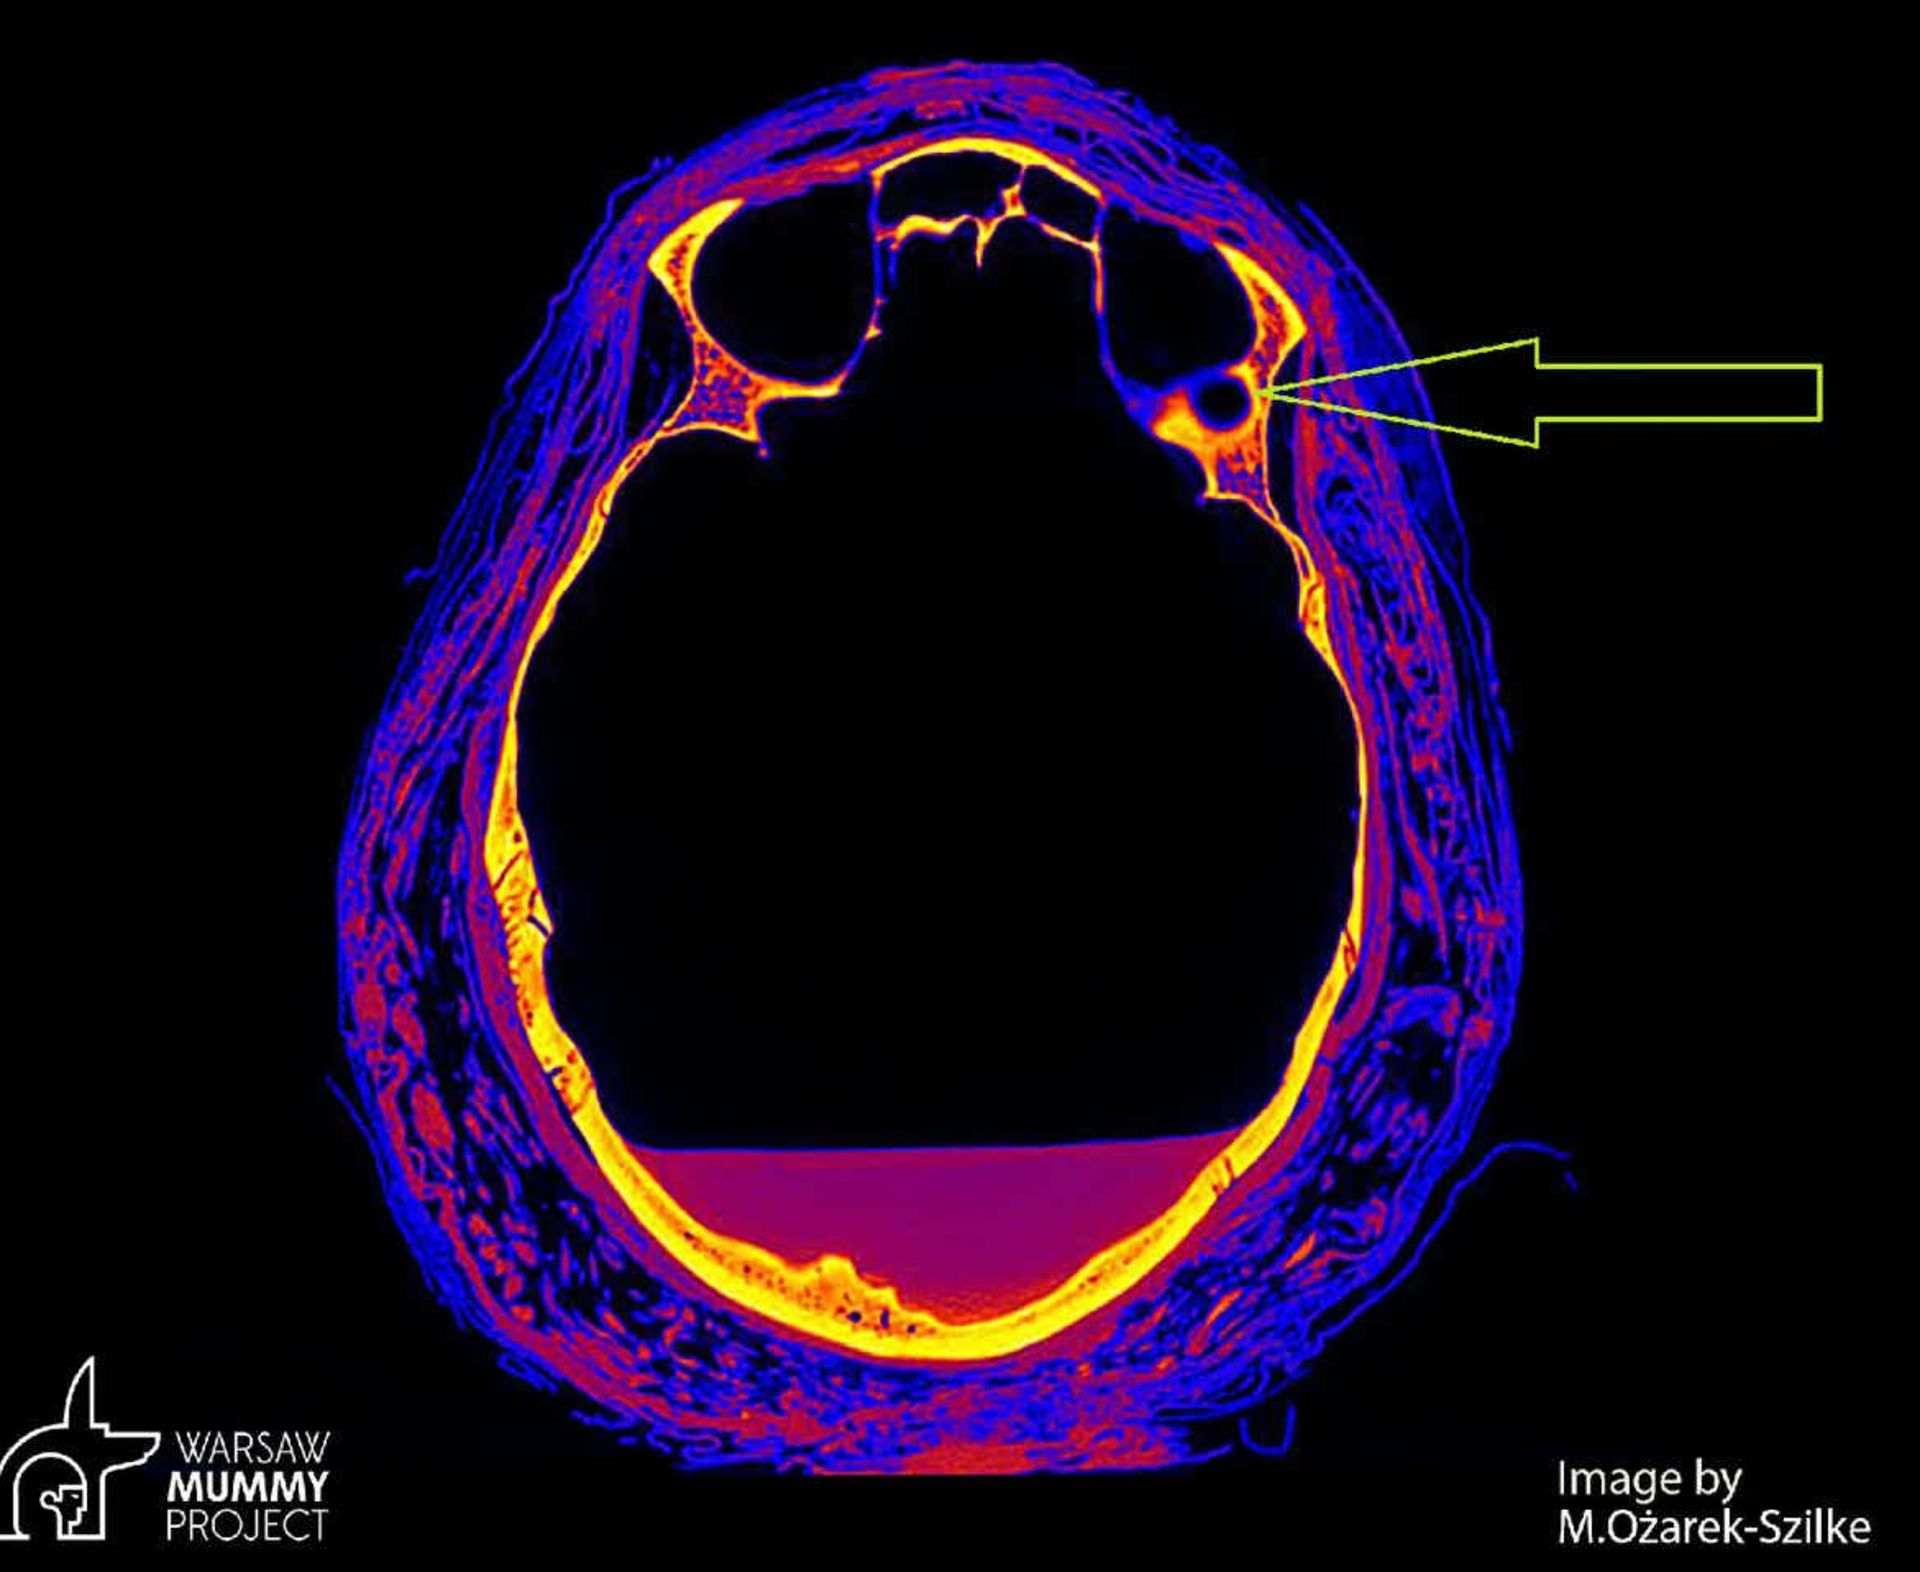

علائم روی جمجمه زن نشان می‌داد که او به سرطان حفره بینی یا نازوفارنکس مبتلا بوده است. سرطان حفره بینی همان‌طور که از نام‌ آن پیدا است، بخشی از بالای گلو بین پشت بینی و پشتِ سقف دهان را درگیر می‌کند. آنچه محققان در تصاویر سی‌تی‌اسکن مشاهده کردند، ضایعه کوچکی به قطر حدود ۷ میلی‌متر به دور فضای توخالی در پشت حدقه‌ی چپ چشم بود.

آسیب‌ ناشی از تومور

بخشی که با پیکان زرد رنگ مشخص شده آسیب‌ ناشی از تومور و محل احتمالی متاستاز را نشان می‌دهد.